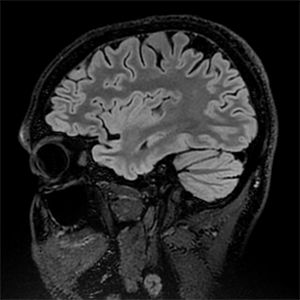

The functional MRI Facility (FMRIF) is a core resource serving the Intramural Research Program. It was initiated in 1999 primarily by the National Institute of Mental Health (NIMH) and the National Institute for Neurological Disorders and Stroke (NINDS). Its function is to serve as a resource by which all NIH institutes can perform Magnetic Resonance Imaging (MRI) studies that further the understanding of healthy and diseased brain anatomy, function and physiology.

The Facility provides a complete environment for stimulus presentation, monitoring and recording subject behavior and physiology while performing functional MRI (fMRI). At present, the Facility has a total of five scanners for the investigation of humans. These scanners consist of 2 General Electric 3 Tesla MRI scanners, one Siemens 3 Tesla MRI scanner, and 2 Siemens 7 Tesla MRI scanners. More information about each of these scanners and the peripheral user devices equipped can be found here.

The staff of the FMRIF continues to be committed to maintaining a world-class fMRI scanning environment, providing capability for exploring brain function, physiology, and morphology in healthy volunteers and clinical populations.